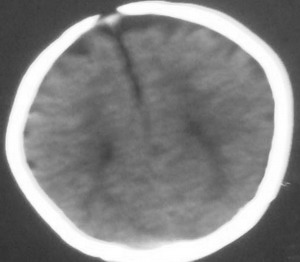

以下是引用杀毒软件在2008-7-29 17:53:00的发言:[br]考虑:胼胝体发育不全,额叶皮质及脑室旁白质萎缩.

以下是引用dyqct在2008-7-30 17:05:00的发言:[br]考虑:1、胼胝体发育不全;[br] 2、肝豆状核变性(双侧豆状核对称性低密度)。

以下是引用同在2008-7-29 20:38:00的发言:[br]胼胝体发育不全.